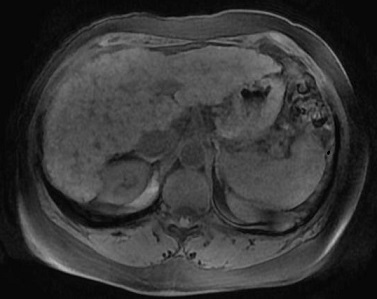

Image IRM de la cirrhose du foie : Cette

technique est moins sensible de diagnostic de la cirrhose du

foie au debut mais bien dans la recherche de petite HCC

. Morphologie de la cirhose du foie sur IRM est

resemble que dans le CT et echographie . Aspect

radiologique IRM en T1 de cirrhose du foie est image

isosignal a bord et parenchyme irregulie

nodulaire et a hyposignal en T2 .

Aspect radiologique IRM en T1

d'une cirrhose du foie . Foie a petit taille

isointense a bord irregulier et splenomegalie

( coupe axiale ) . |

Cirrhose du foie en

coupe axiale IRM en T2 . Foie est

hyposignal |